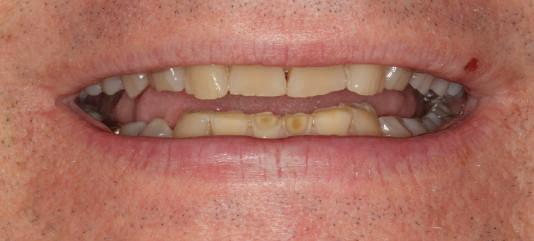

Reabilitările implantare complexe pot include abordări în etape, implicând de obicei extracţia seriată a dinţilor irecuperabili. Se evită astfel necesitatea protezelor mobilizabile prin menţinerea dinţilor naturali în cursul vindecării şi împiedică încărcarea imediată a implanturilor plasate în osul grefat. Un dezavantaj major constă în recesia gingivală. Acest articol dezbate diverse abordări pentru gestionarea modificărilor gingivale şi sugerează modificări de protocol în cursul fazei de planificare terapeutică cu implanturi.

Pla una susţinută de implanturi pot fi îndelungate atunci când obiectivul constă în evitarea aplicării unei proteze mobilizabile. Una dintre opţiuni este reprezentată de încărcarea imediată a implanturilor cu o restaurare totală provizorie. Când acest lucru nu este posibil, trebuie implicate metodologii pentru evitarea încărcării imediate. Mulţi dentişti restauratori şi chirurgi orali pot opta atunci pentru extracţiile seriate, astfel încât pacientul să nu rămână deloc fără dinţi. Acest protocol, denumit adesea abordare stadializată, protocol de extracţie în serie sau tratament multifazic a fost formulat

Deşi poate varia de la pacient la altul, acest tip de tratament implică de obicei stadii multiple de inserare a implanturilor în cursul cărora dinţii reziduali dar irecuperabili sunt menţinuţi ca bonturi temporare pentru a susţine restaurări provizorii fixe. Odată cu realizarea conexiunii dintre bonturi şi primul set de implanturi, dinţii reziduali se extrag şi se efectuează o a doua etapă de inserţie a implanturilor. După vindecarea celui de-al doilea set sau a setului final de implanturi, se pot realiza procedurile protetice pe implanturi pentru a finaliza terapia. Cavallaro & Greenstein au împărţit acest protocol în două clasificări: clasa I, cu toate implanturile inserate în cursul primei etape chirurgicale; şi clasa a II-a cu două sau mai multe etape de inserare a implanturilor pentru a genera suficientă susţinere implantară.

Dacă planul de tratament etapizat are una, două sau mai multe faze implantare, principalele dezavantaje ţin de

durata tratamentului şi implicarea mai multor etape chirurgicale. Avantajele sunt numeroase, incluzând: abilitatea de a utiliza o restaurare provizorie fixă pe toată durata tratamentului şi a fazelor de vindecare, ghidajul simplificat pentru inserarea implanturilor, menţinerea funcţiei masticatorii şi managementul ţesutului moale. În pofida progreselor precum planificarea virtuală, încărcarea imediată şi suprafeţele îmbunătăţite ale corpurilor implantare, vindecarea ţesutului moale nu este încă predictibilă în mod curent. Deşi pierderea de până la 1mm din osul marginal în cursul primului an după conexiunea bontului era acceptabilă odinioară, a devenit evident că aceasta poate însemna totodată pierderea de ţesut moale în aceeaşi perioadă sau în anii următori. Indiferent că pierderea tisulară este imediată sau ulterioară, succesul tratamentului este judecat din prisma funcţiei şi a esteticii dentare dar şi a ţesutului moale.

Managementul ţesutului moale în abordarea etapizată poate fi imprevizibil şi prezintă provocări estetice, în principal recesia gingivală.

Acest articol va prezenta câteva exemple de cazuri cu abordare etapizată în cazul unor recesii de ţesut moale în jurul bonturilor.

Cazurile sunt organizate prin modificări ale planului de tratament, care variază de la menţinerea gulerului auriu vizibil al bontului şi până la refacerea bonturilor şi a elementelor turnate.

Cazul (1)

Reprepararea intraorală a bonturilor Acest pacient prezenta dentiţia maxilară compromisă, refuzând proteza mobilizabilă. Prin abordarea în etape, se menţin o parte din bonturile dentare naturale; s-a observat recesie în momentul amprentării pentru cel de-al doilea grup de implanturi.